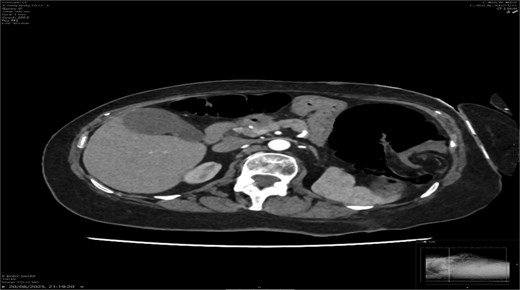

A contrast-enhanced CT scan of the abdomen demonstrated a whirl sign at the mesenteric root (Figs 1 and 2), dilated transverse colon with a transition point at the splenic flexure (Fig. 3), and no evidence of ischemia or perforation (Fig. 4). These findings were consistent with TCV.

Axial CT showing dilated transverse colon at the splenic flexure.